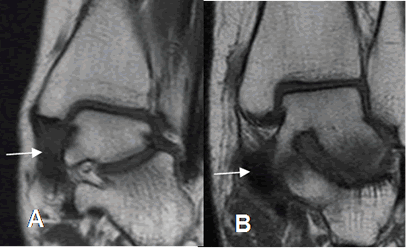

Fig 93. Pinzamiento anterolateral.

A: TAC reconstrucción coronal, B: RM coronal en T1 y C: RM coronal en STIR. Lesión osteocondral en la parte superoexterna del talo.